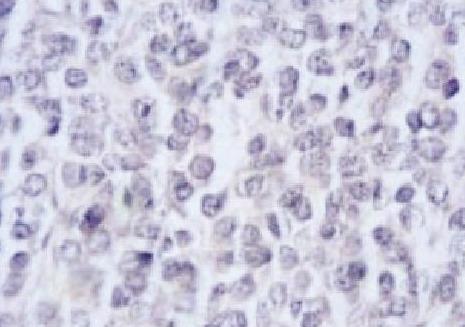

Cette jeune patiente de 14 ans, sans antécédents particuliers, avait depuis 2 mois une tuméfaction de l’angle et de la branche montante de la mandibule sans troubles de la sensibilité labio-mentonnière ni adénopathies cervicales. La tomodensitométrie et l’imagerie par résonance magnétique mandibulaire (fig. 1 ) montraient une ostéolyse mandibulaire avec une importante extension dans les parties molles, surtout du côté lingual, et une réaction périostée spiculée. L’analyse de la biopsie (fig. 2 ) notait une prolifération tumorale constituée de petites cellules rondes exprimant en immunohistochimie le CD99, affirmant le diagnostic de sarcome d’Ewing. Selon le protocole Euro-Ewing 99, chimiothérapie et chirurgie étaient associées, permettant la régression de la tumeur mandibulaire avec, à 6 mois, un contrôle locorégional satisfaisant et l’absence de métastase à distance. La surveillance était maintenue tous les 3 mois.